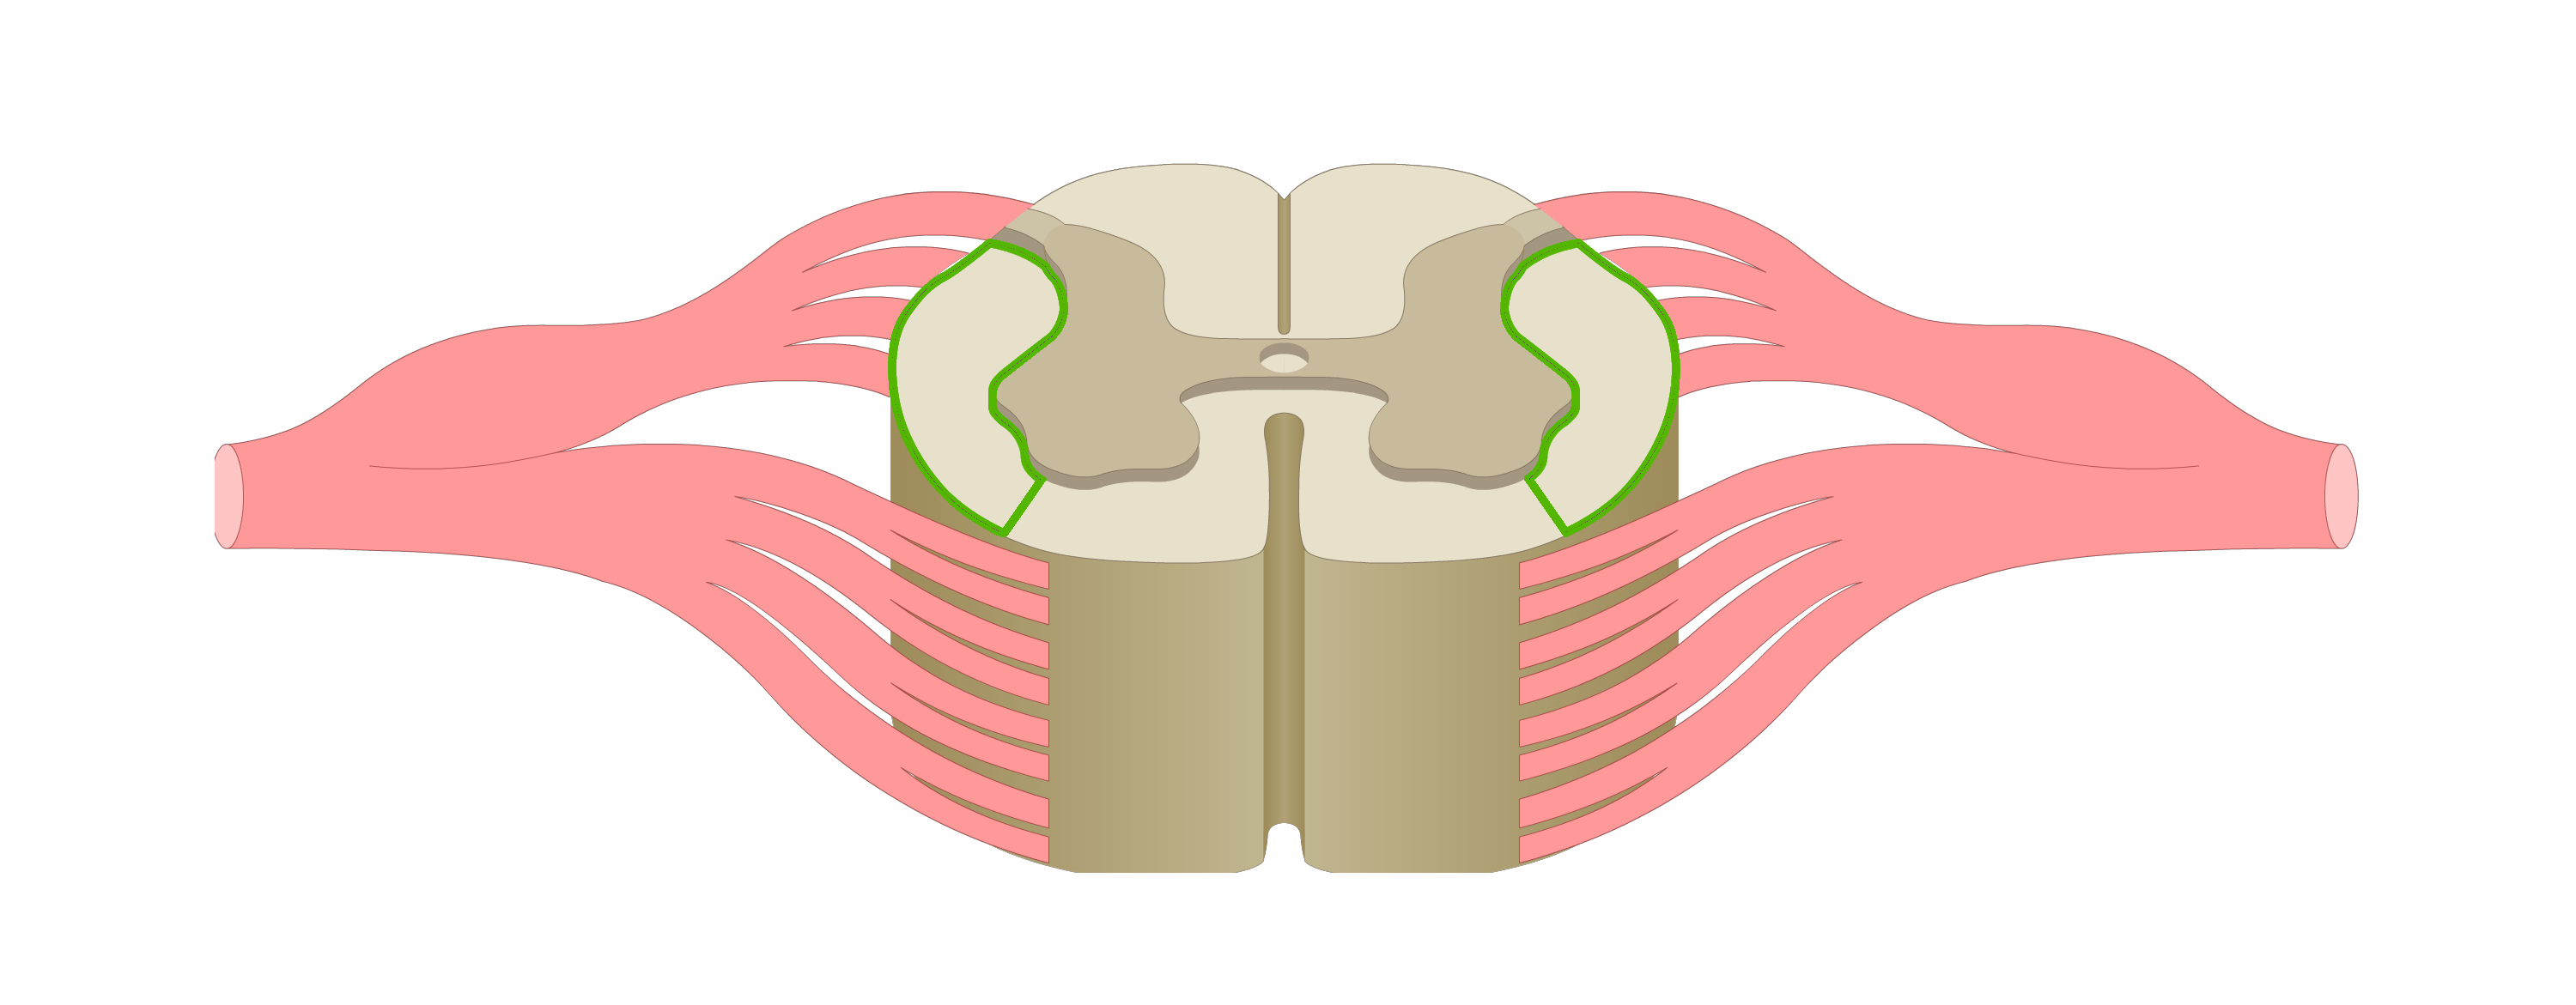

motor tracts

sensory tracts

dorsal root ganglion

dorsal horn

lateral horn

ventral horn

dorsal funiculus

lateral funiculus

ventral funiculus

central canal

ventral median fissure

dorsal median sulcus